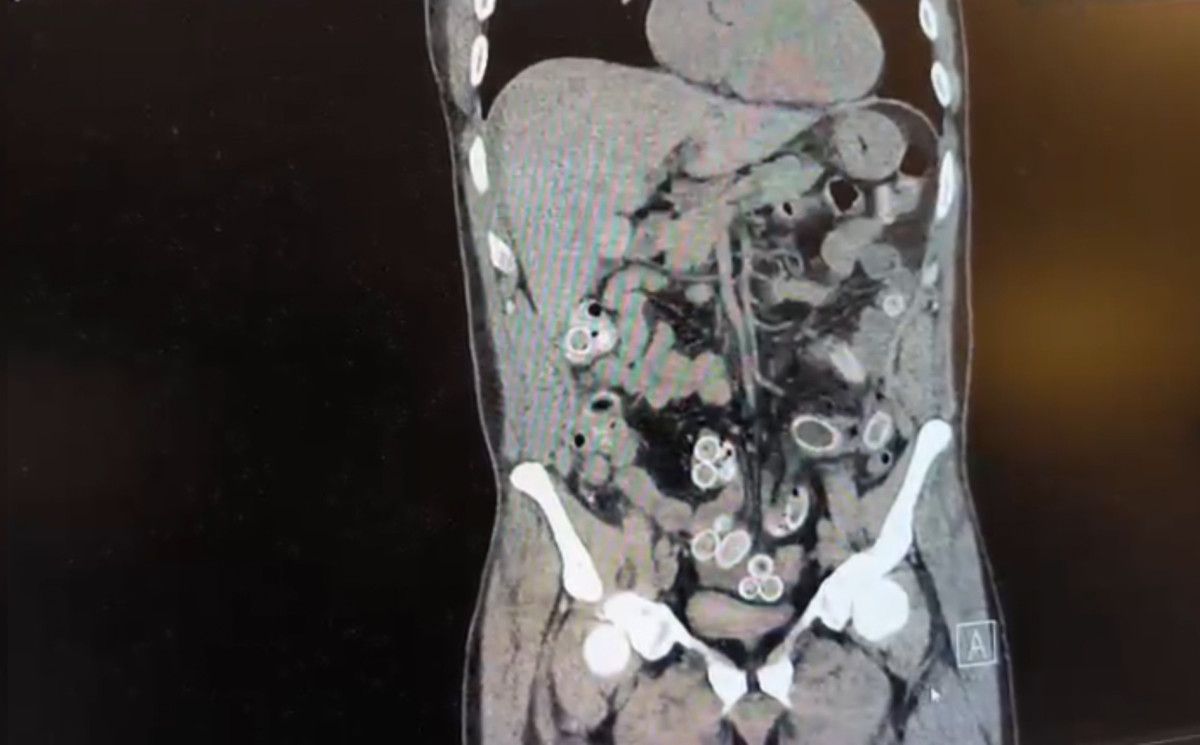

Yapılan muayenenin ardından Cüneyt G.’nin tomografisi çekildi. Şüphelinin mide ve bağırsaklarında yabancı madde tespit edilmesi üzerine hastane yetkilileri durumu polis ekiplerine bildirdi.

İhbar üzerine çalışma başlatan Beşiktaş Asayiş Büro Amirliği ekipleri, doktorlarla görüşme gerçekleştirdi. Doktorların değerlendirmesi sonrası ameliyata alınan Cüneyt Ç.’nin bağırsaklarından, toplam ağırlığı 259,7 gram olduğu öğrenilen 49 esrar macunu çıkarıldı.